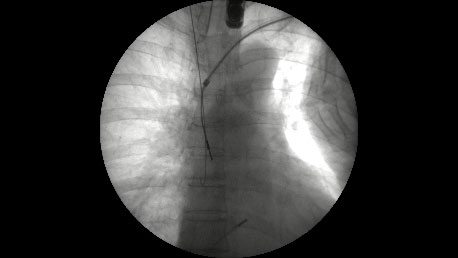

当院が施設認定を受け、「経静脈電極抜去術(レーザーシースを用いるもの)によるリード抜去」の第一例目を2016年6月9日に開始して1年以上経過しました。これまで他県に依頼してきた手技が、鹿児島でもようやく可能となり、南九州では初めてのことでした。第一例目開始から2017年6月2日までの初期の1年間で、15症例、計28本のリード抜去術を施行し、現在まで全例のリード抜去に成功しています。

リード抜去は心タンポナーデ、鎖骨下と上大静脈の血管損傷や血気胸などの重篤な合併症があり、すぐに開胸して止血術を行わなければならないために心臓血管外科の待機下で施行が必要です。